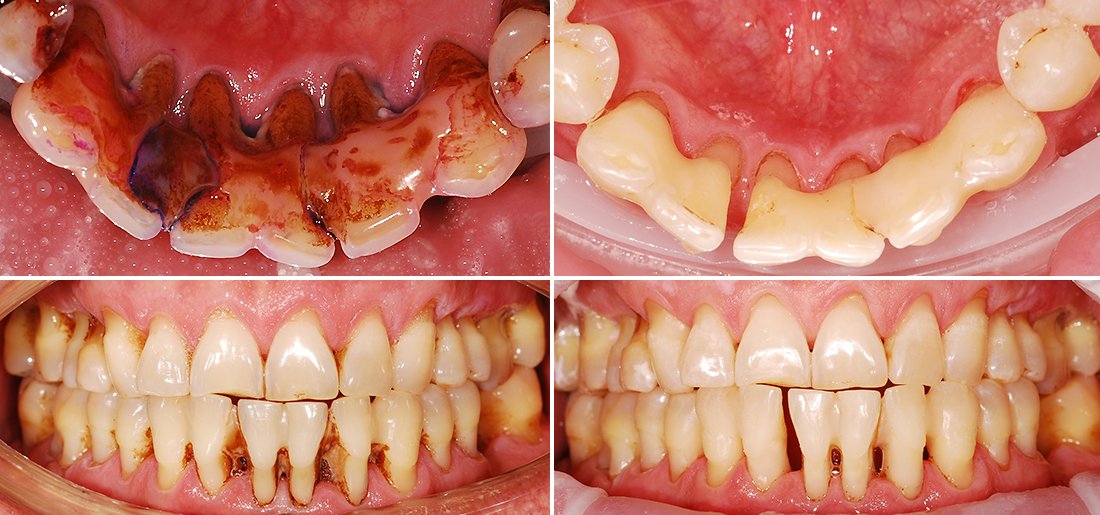

- Кровоточивість ясен: особливо при чищенні зубів або вживанні твердої їжі.

- Чутливість: зуби раптом реагують на холодне, гаряче, кисле.

- Зміна кольору ясен: від блідо-рожевого до червоного або навіть синюшного.

- Пародонтит: інфекція, яка атакує ваші ясна. Дістає в глибині, вириваючи з коренем.

Наслідки, яких варто остерігатися

Якщо залишити все на самоплив, ясно — отримаєте серйозні сертифіковані неприємності. Зуби можуть хитатися, а це вже не жарти.

- Втрата зубів: ось це буває боляче, і буквально, і в переносному сенсі.

- Інфекції: відкриті ділянки роблять шлях для бактерій. Це війна, війна мікробів проти вас.